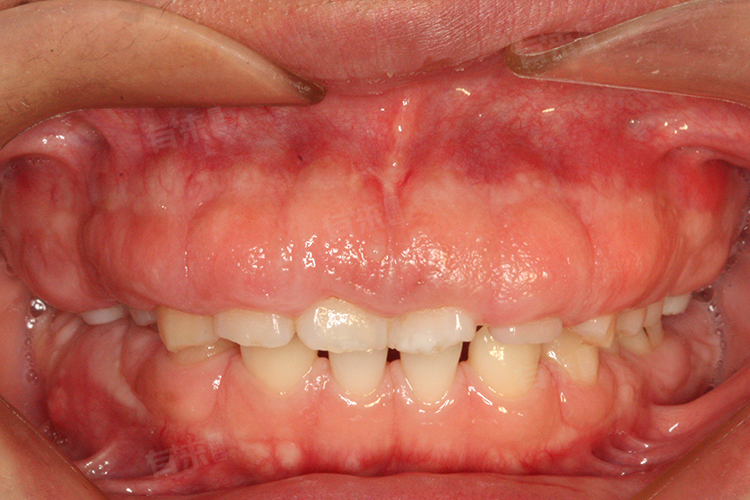

6岁儿童牙龈红肿发炎是常见的口腔问题,可能由多种因素引起,如不良的口腔卫生习惯、牙龈炎等。家长需要采取适当的措施来缓解孩子的不适,包括温盐水漱口、保持口腔卫生、避免刺激性食物等。